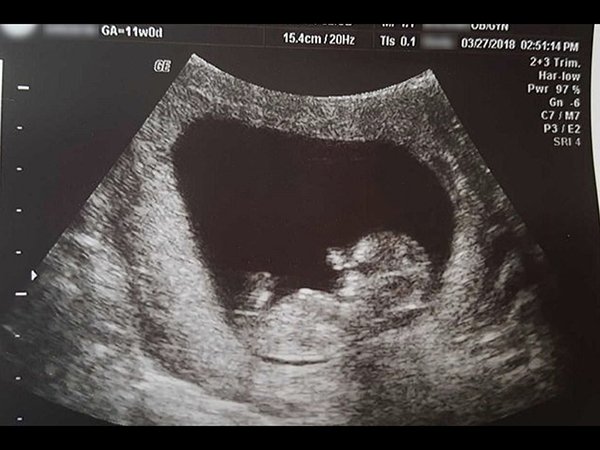

കരളലിയിക്കും ഗര്ഭസ്ഥശിശുവിന്റെ ചിത്രവുമായി അമ്മ

നഷ്ടം എന്നത് എല്ലാവരേയും വളരെയധികം ദു:ഖത്തിലാക്കുന്ന ഒരു വാക്ക് തന്നെയാണ്. അത് വലുതെന്നോ ചെറുതെന്നോ എന്നത് വിഷയമല്ല. സ്വന്തം കുഞ്ഞിനെ നഷ്ടപ്പെടുമ്പോഴുള്ള ഒരു അമ്മയുടെ ദു:ഖത്തിന് പകരം വെക്കാന് ഒന്നിനുമാവില്ല എന്നതാണ് സത്യം. വെറും പതിനാല് ആഴ്ച മാത്രം പ്രായമുള്ളപ്പോള് ഗര്ഭത്തില് നിന്ന് നഷ്ടപ്പെട്ട തന്റെ സ്വന്തം കുഞ്ഞിന്റെ ചിത്രം സമൂഹ മാധ്യമത്തില് അതീവ ദു:ഖത്തോടെ പങ്കു വെച്ചിരിക്കുകയാണ് ഈ അമ്മ. ആരോഗ്യപരമായ കാരണങ്ങള് കൊണ്ട് ഗര്ഭഛിദ്രം നടത്തേണ്ടി വന്ന ഒരു നിര്ഭാഗ്യകരമായ അവസ്ഥയാണ് ഈ അമ്മക്ക് പറയാനുള്ളത്.

തന്റെ ഗര്ഭസ്ഥശിശുവിന്റെ ചിത്രം സോഷ്യല് മീഡിയയില് പങ്കു വെച്ച് തന്റെ അനുഭവം മറ്റുള്ള അമ്മമാര്ക്ക് മുന്നില് തുറന്ന് കാണിക്കുകയാണ് ഇവര്. ഇവരുടെ നഷ്ടം ഒരിക്കലും നികത്താനാവാത്തതാണ് എന്നത് ഇതിലൂടെ വീണ്ടും വീണ്ടും ഓരോ സ്ത്രീയേയും ഓര്മ്മിപ്പിക്കുകയാണ് ഇതിലൂടെ. ഈ ചിത്രം കാണുന്ന ഏതൊരാളുടേയും മനസ്സലിയും എന്ന കാര്യത്തില് സംശയം വേണ്ട.

ഈ അമ്മ തന്റെ പതിനാലാം ആഴ്ച മാത്രം പ്രായമുള്ള കുഞ്ഞിന്റെ ചിത്രമാണ് സമൂഹമാധ്യമത്തില് പങ്കെ വെച്ചിട്ടുള്ളത്. ശരിക്കും ഒരു ശിശുവിന്റെ രൂപം മുഴുവനായി മാറിയിട്ടുണ്ടായിരുന്നു ഈ ഗര്ഭസ്ഥശിശുവിന്. നാല് ഇഞ്ച് വലിപ്പവും 0.05 പൗണ്ട് തൂക്കവും ഈ ശിശുവിനുണ്ടായിരുന്നു.